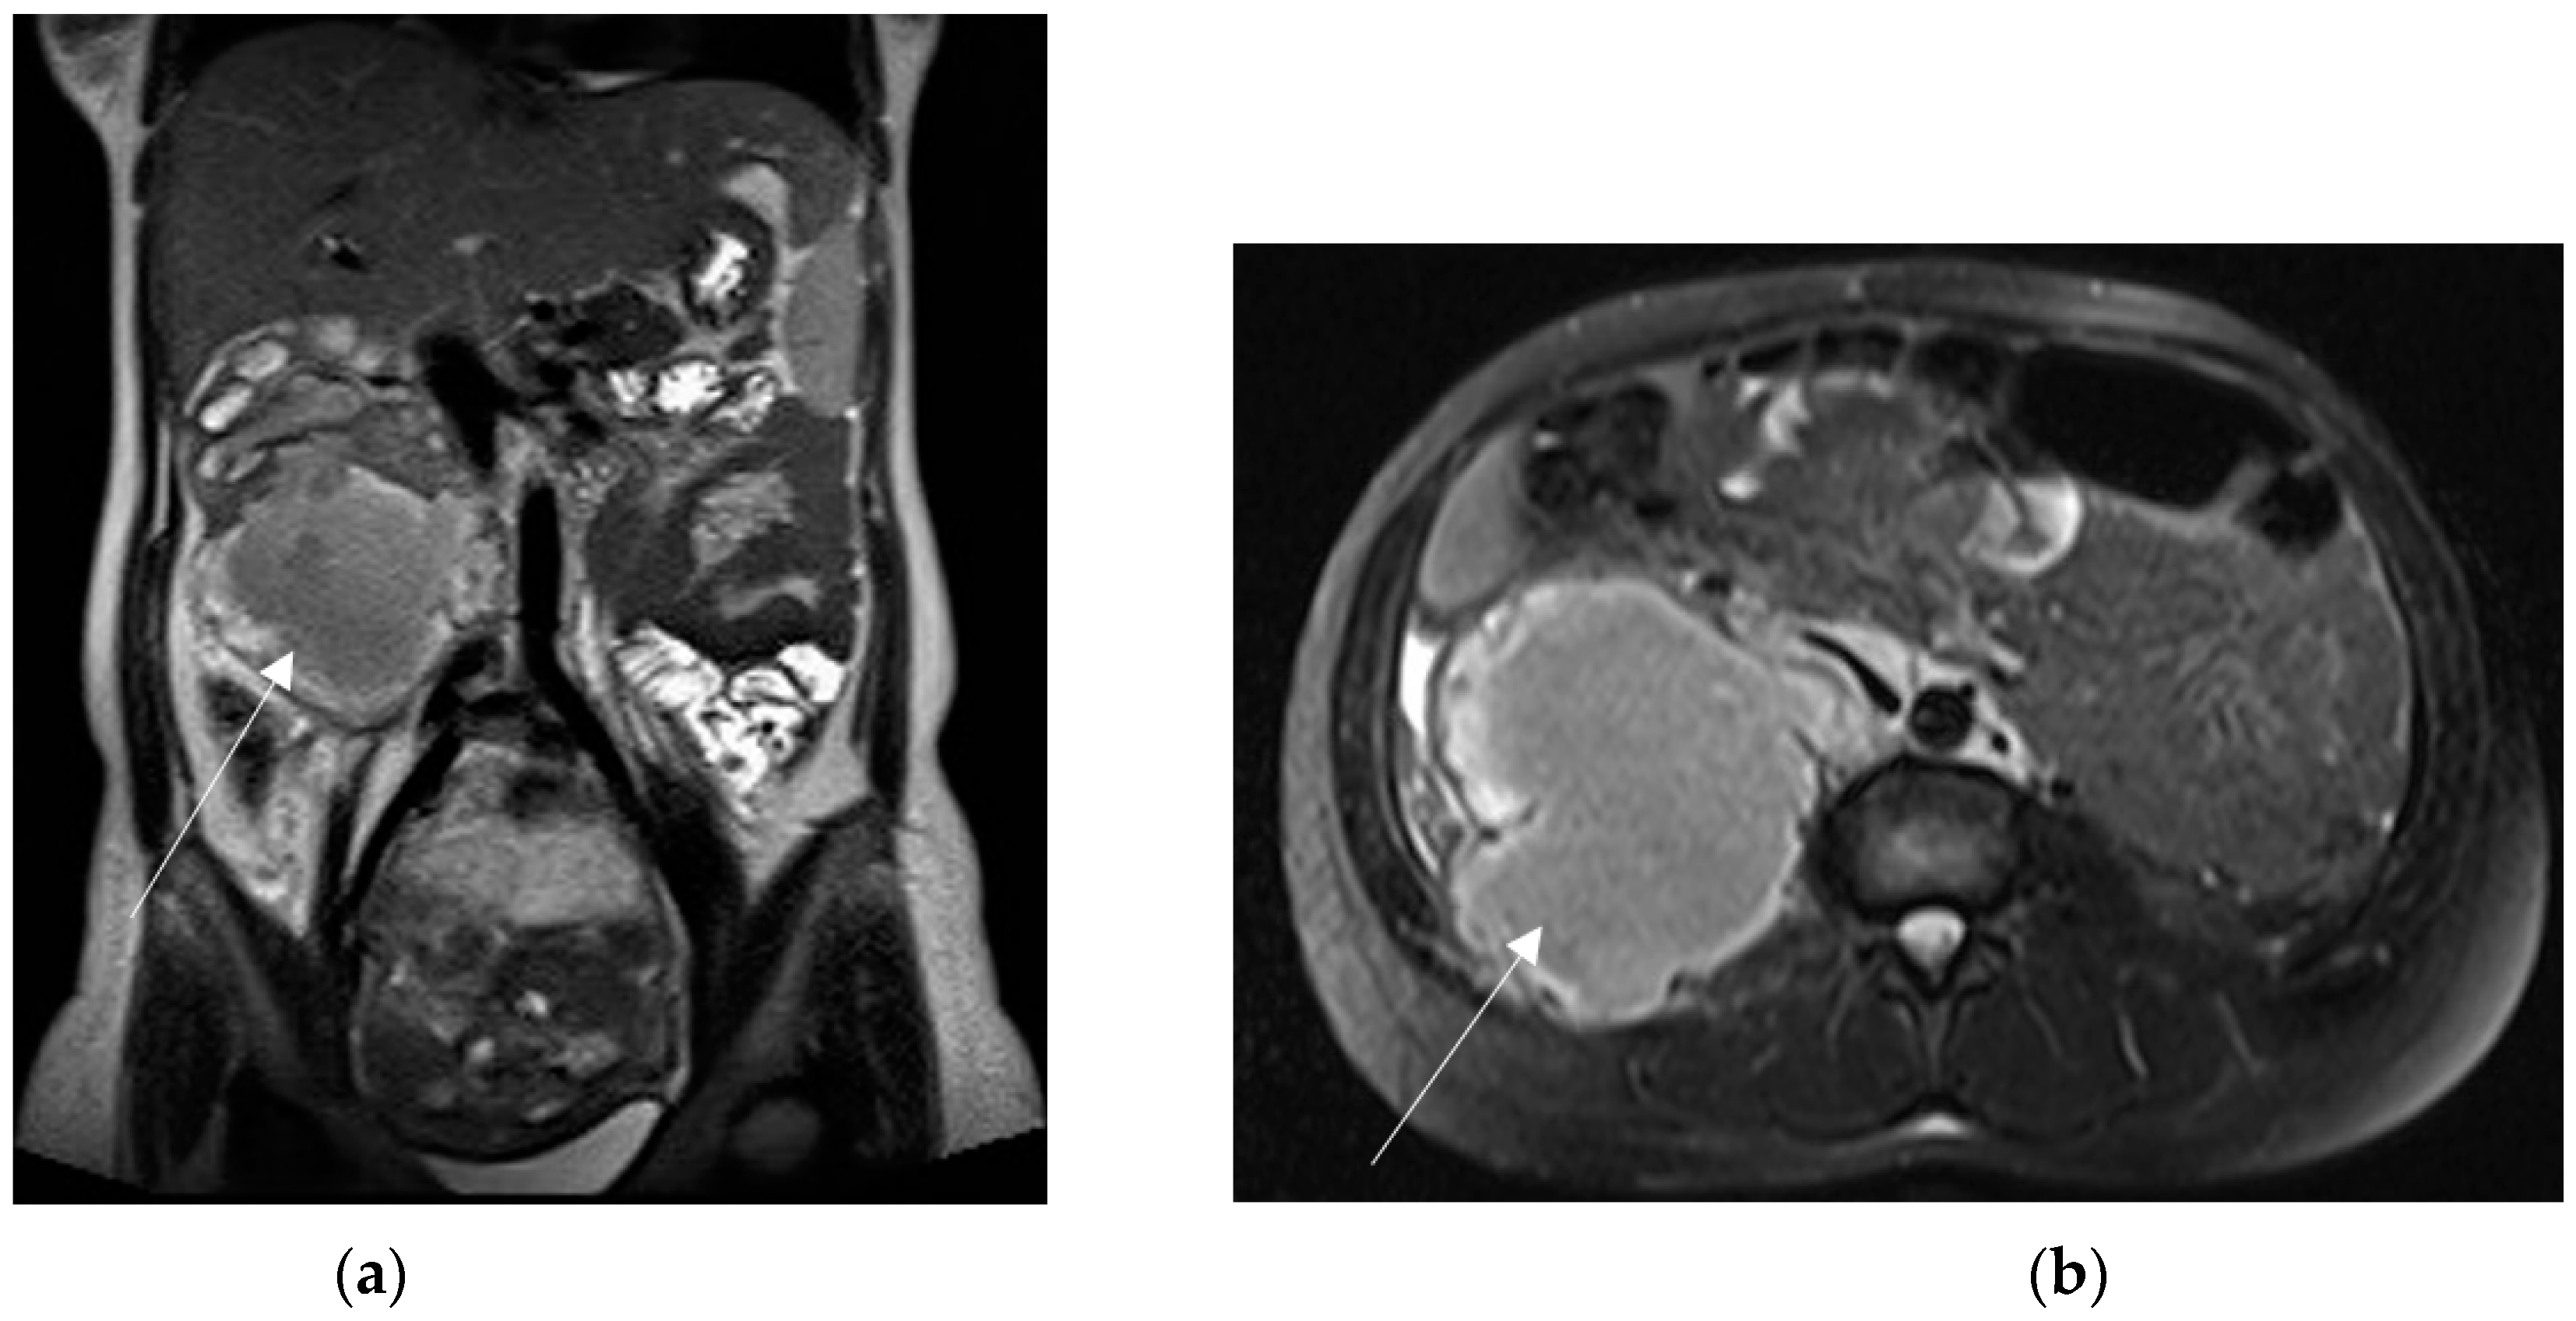

Most ovarian masses diagnosed in pregnancy are benign and are spontaneously resolved (Figure 9). Surgical management is warranted when masses are suspicious for malignancy, at risk for torsion or clinically symptomatic [3].

Figure 9.

Left adnexal torsion in 28-year-old patient at 35 weeks of gestation. Axial (a) and coronal (b) T2-weighted images show left cystic formation of about 8 cm (arrow) that has undergone torsion, compressed between the gravid uterus and the abdominal wall.